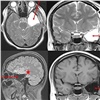

До операции пациент проходит ряд специфических обследований: длительный видео-электроэнцефалографический мониторинг, воздействия, провоцирующие эпилептический приступ: гипервентиляцию, фотостимуляцию на фоне отмены антиконвульсантов, депривацию сна (недостаток или полное отсутствие сна), исследование электроэнцефалограммы больного в состоянии физиологического сна. Комплексное обследование помогает врачам установить локализацию участка мозга, который провоцирует приступы. Также с пациентами работает нейропсихолог для оценки рисков ухудшения памяти и когнитивного статуса в случае проведения операции.

Затем консилиум, состоящий из нейрохирурга, невролога, нейрофизиолога, оценивает соотношение рисков и успешного прогноза исхода операции и принимает окончательное решение о хирургическом вмешательстве.